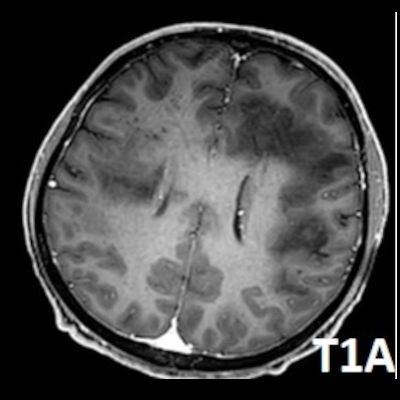

- Bilateral asimetrik subkortikal ve derin beyaz cevherde T1 ağırlıklı görüntülerde belirgin hipointens (oklar), T2A görüntülerde hiperintens (oklar), gri cevhere bakan kesimi düzgün (oklar), DAG’de hiperintens (ok) lezyonlar izlendi. Lezyonlarda T2/FLAIR uyumsuzluğu vardı (ok). Serebellar beyaz cevherde dentat nukleusu koruyan hilal işareti görüldü (ok başı). SWI sekansta sol motor kortekste hipointens kronik glioinflamatuar reaksiyon ile uyumlu sinyal değişikliği izlendi (ok başı).

- PML lezyonları, T1A görüntülerde belirgin hipointenstir. Gri cevhere bakan yüzleri keskin olup T2/FLAIR uyumsuzluğu önemli özelliğidir.